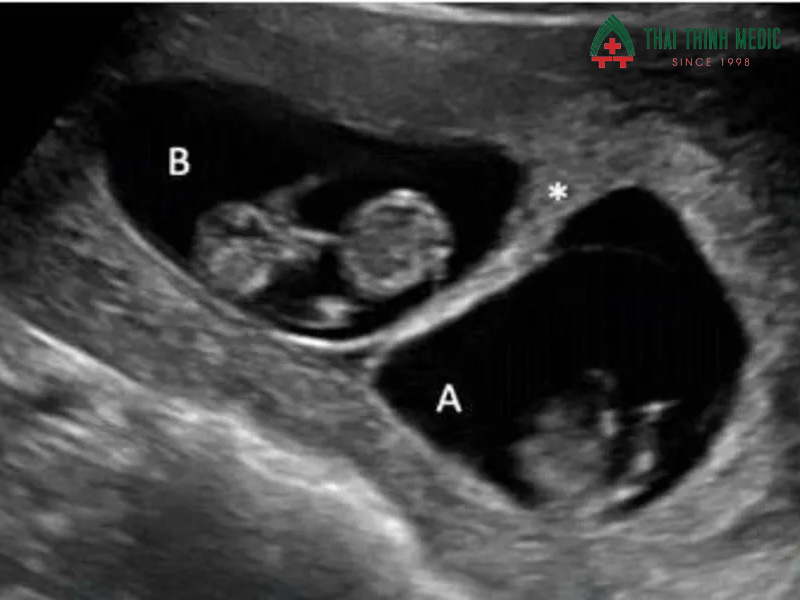

Túi và nhau thai

Túi thai và bánh nhau cung cấp thông tin quan trọng về môi trường phát triển của thai nhi. Bác sĩ sẽ kiểm tra vị trí, kích thước, sự bám của nhau thai và lượng dịch ối. Đây là yếu tố quyết định đến sức khỏe tổng thể của thai nhi, giúp phát hiện sớm các vấn đề như nhau bám thấp, thai ngoài tử cung hoặc thiểu ối.